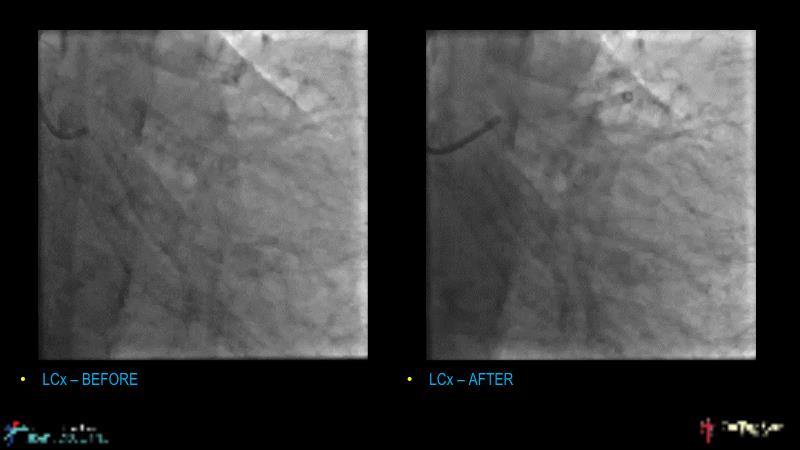

A hybrid approach in complex PCI: can DES and DCB be complementary?

Watch this case-based session to follow discussion about how to choose between DES & DCB, how both can be complementary in diffuse disease as well as in complex PCI, and how physiology and imaging can help guiding PCI, and follow a patient's treatment live.

- To learn the tips and tricks in performing complex PCI intervention with DES and/or DCB